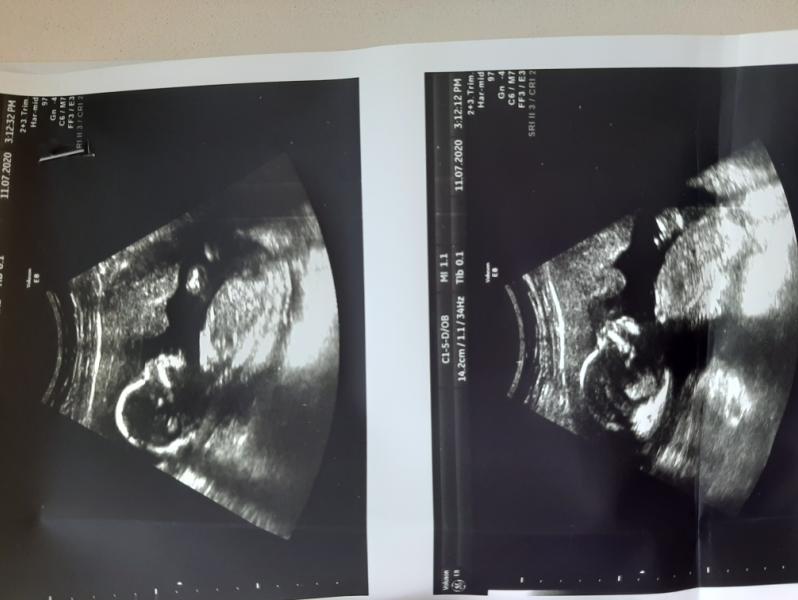

УЗИст не увидела каких-либо признаков мужчины, предположила, что все-таки у нас девочка)

Ощущения, когда отчётливо видишь своего, такого родного, маленького, но уже активного малыша, конечно, незабываемые!

я от чувств расплакалась и всё-таки пожалела, что не взяла с собой мужа(

Слава богу, что физически и эмоционально тяжелый 1 триместр уже позади. Сейчас даже жить стало спокойнее. А после сегодняшнего УЗИ тем более)))

Увидела здесь много хороших отзывов о клинике "Арника", находится на Красной площади. Была сегодня там, все очень понравилось)